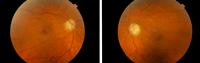

Figura 1. Angiografía fluoresceínica en fase venosa precoz (A y B) y fondo de ojo (C) . En el ojo izquierdo se aprecian las líneas horizontales con franjas hipofluorescentes e hiperfluorescentes correspondientes a los valles y crestas (cortesía Dra. Fossas-Dr. Arruga).